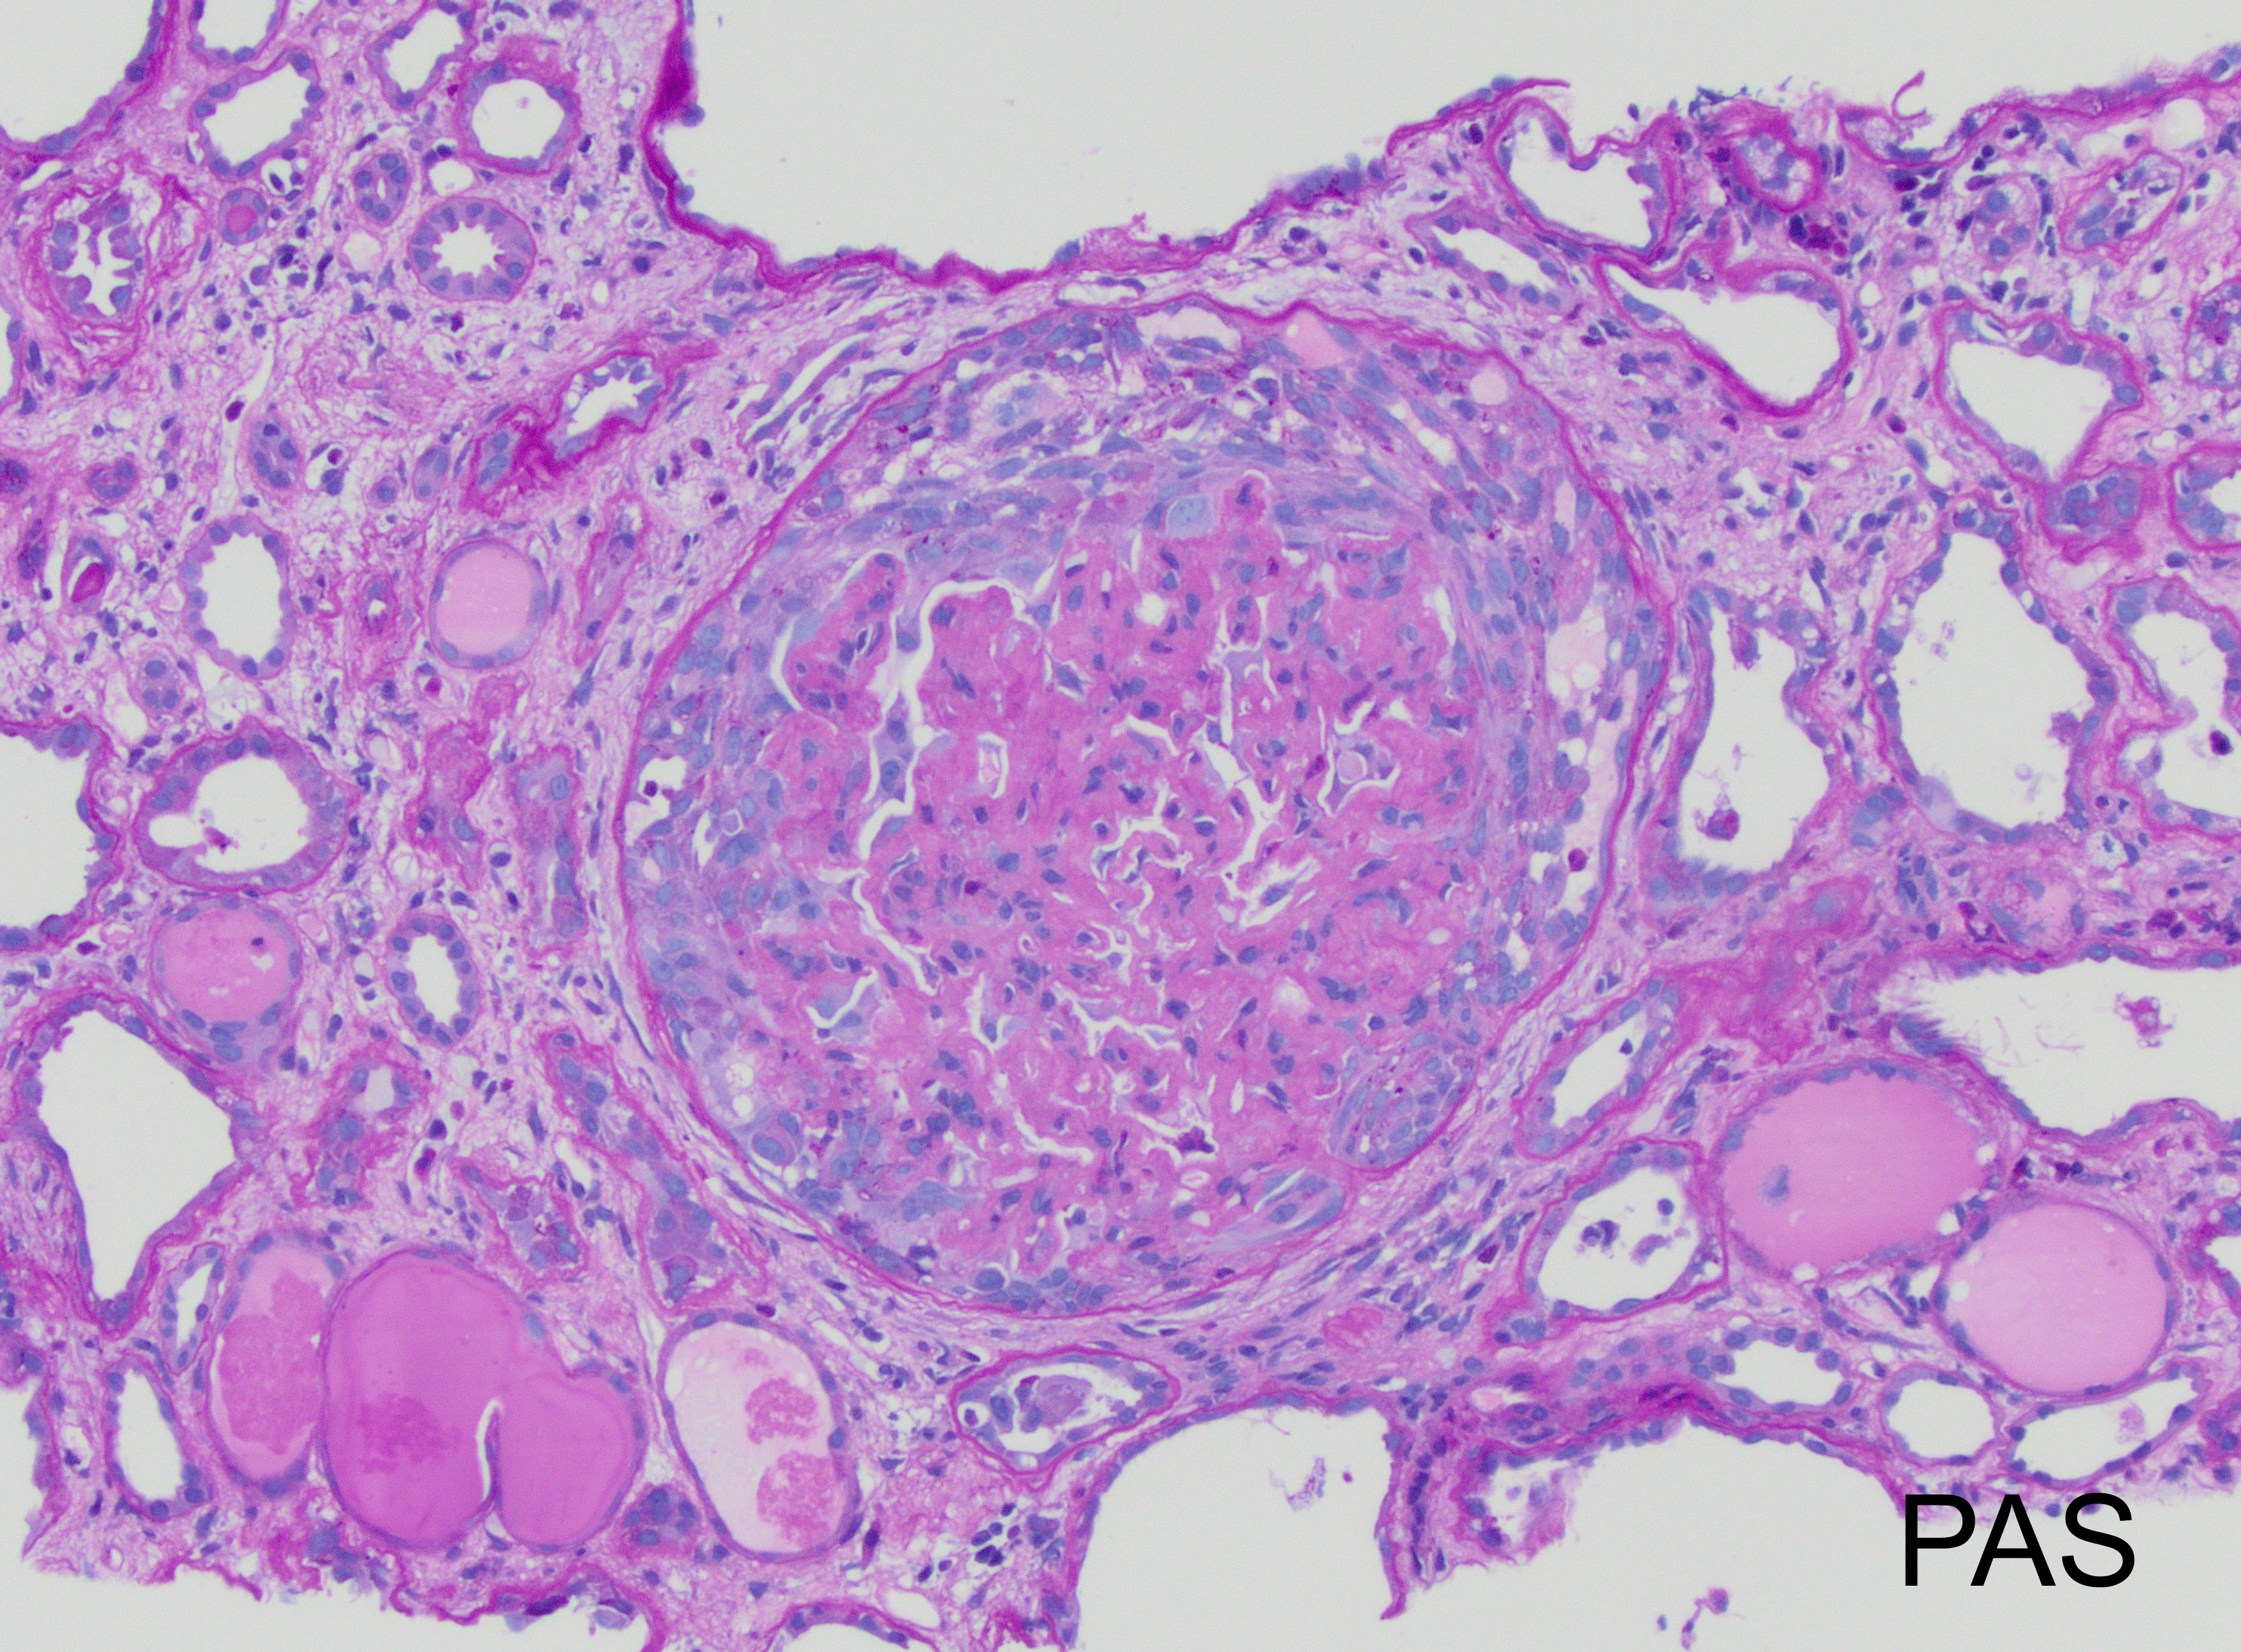

The patient is 32 year-old female with acute kidney injury and nephrotic range proteinuria. A renal biopsy showed diffuse global mesangial and capillary wall expansion by eosinophilic weakly PASH positive material (Silver stain showed in Figure 1), with cellular crescents in 40% and fibrocellular crescents in 5% of the glomeruli. A Congo red stain failed to show apple-green birefringence under polarized light (Figure 2). There was intense immunofluorescence staining with IgG, IgA, C3, and light chains (Figure 3). Electron microscopy showed fibrils with 25 nm average diameter (Figure 4).

FGN is a rare form of glomerulonephritis (less than 1% in native renal biopsies), which diagnosis is historically defined by glomerular deposits of Congo red negative, randomly arranged, straight fibrils without a hollow center that measure between 10-30 nm in diameter (larger than amyloid fibrils) and stain for immunoglobulins. The fibrils are localized in the mesangium and/or along the glomerular basement membrane.

By light microscopy, the most commonly reported patterns of injury are membranoproliferative and mesangial proliferative, with focal crescents in 17-50% of the cases (like in this case which showed less than 50% of glomeruli involved; figure). The deposits result in expansion of the mesangium and/or capillary walls by eosinophilic material that is pale with periodic acid-Schiff, nonargyrophilic, and negative for Congo red. By immunofluorescence, “smudgy” mesangial and/or capillary wall intense staining for IgG (most often IgG4 subclass), usually with C3, kappa and lambda light chains is noted. IgM, IgA and C1q show weaker positive staining in some cases.